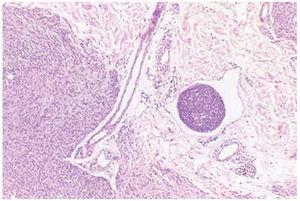

De los 8 pacientes estudiados, siete eran mujeres. La edad media fue de 26 años. Macroscópicamente las lesiones pigmentadas presentaron un diámetro medio de 0,4 cm, con contornos regulares y no se apreció discromasia en ninguno de ellos. En los casos 1, 2, 3, 4 y 7 (tabla 1) los pacientes refirieron que la lesión cutánea pigmentada estaba presente desde el nacimiento y/o primera infancia. Histológicamente estos 5 casos cumplían los requisitos de nevo congénitos2,6. Dos de ellos fueron intradérmicos (casos 1 y 4) y tres compuestos (casos 2, 3 y 7). En estos 5 casos se observó, en la dermis reticular, en el seno de la población melanocítica, la presencia de estructuras vasculares linfáticas que contenían en su luz celularidad de hábito melanocítico que adoptaban un patrón arquitectural de masas polipoides (fig. 1) con un revestimiento endotelial de la superficie interna. En el caso número 4 este revestimiento endotelial era parcial, dando la apariencia de que las células melanocíticas del propio nevo empujaban y en algún área sustituían o lesionaban el revestimiento endotelial (fig. 2). En el caso 1 existían además estructuras vasculares linfáticas distantes a la lesión con melanocitos en su luz en forma de agregados irregulares (fig. 3).

Fig. 3.--Nido sólido melanocítico intravascular. (Hematoxilina-eosina, ×60.)